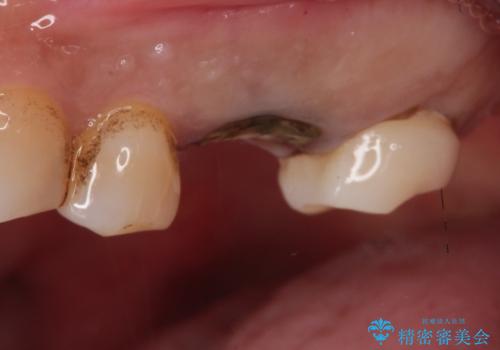

【歯牙破折】インプラントによる咬合回復

- 痛みを主訴に来院されました。

歯牙の破折を認めたため抜歯をし、インプラントにて咬合回復をしました。

抜歯後、骨増生を行ったのちインプラントを埋入しています。